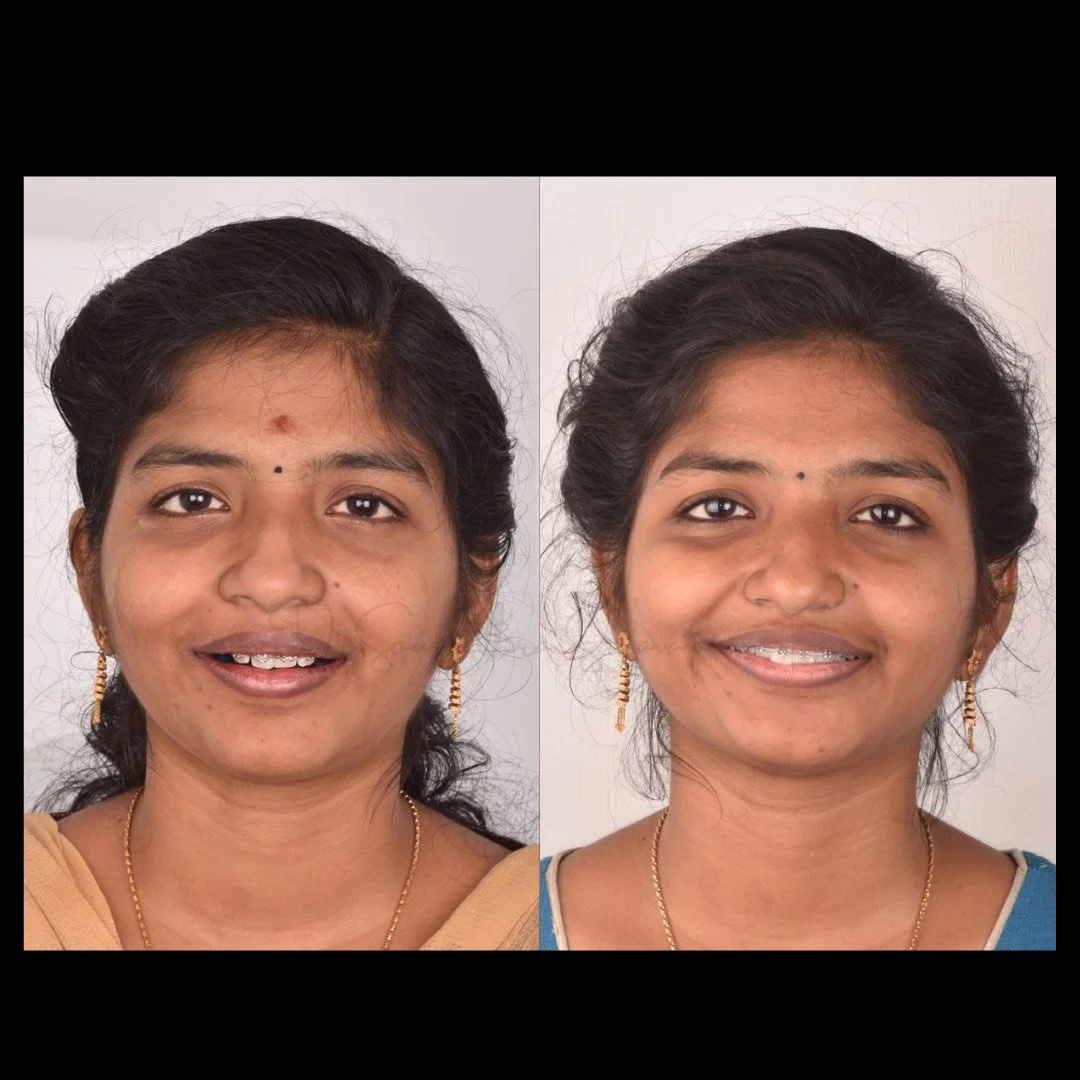

smile makeover

Smile Journey!

May be it is too simple to treat but the way this smile makeover made a difference in her life is immense! thats how wonderful smile curves are created!